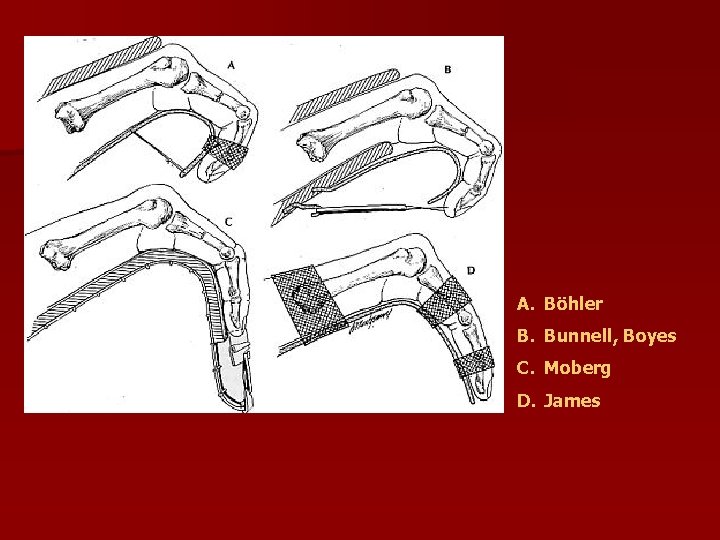

A. Böhler B. Bunnell, Boyes C. Moberg D. James